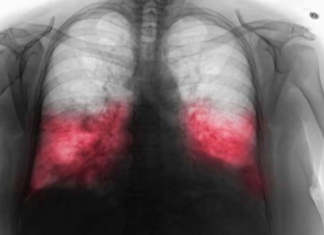

Stručnjak našeg časopisa istaknuo je važno opažanje: nealkoholna masna bolest jetre, stanje u kojem jetra gubi sposobnost pravilnog funkcioniranja, otežava proces detoksikacije i eliminaciju toksina iz našeg tijela. To može dovesti do razvoja akni, prištića, peruti, lomljivih noktiju i dugotrajnog svrbeža. Stručnjak ističe važnost dobrog kolesterola u održavanju optimalnih tjelesnih funkcija.

- Ključno je razumjeti da kolesterol nije protivnik kojeg je stvorila priroda. Naprotiv, služi raznim bitnim svrhama u ljudskom tijelu, uključujući sintezu hormona i stvaranje staničnih membrana. Komplikacije mogu nastati zbog prekomjerne količine kolesterola lipoproteina niske gustoće (LDL), također poznatog kao “loš” kolesterol. Osim toga, napravio je revolucionarno otkriće o procesima koji uzrokuju porast razine triglicerida.